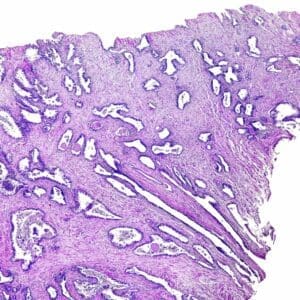

Under local anesthetic, a lubricated ultrasound probe is placed in the rectum allowing the physician to see the shape and size of the prostate—along with any apparent abnormalities or shadows that may indicate cancer. After the prostate gland is injected with numbing anesthetic, slim needles are used to gather samples from several zones of the prostate including suspicious-looking areas (although not all prostate cancers are visible). The collected tissue samples are sent to a pathologist who will examine them to determine if cancer is present.

Cancer Grading

Grading refers to the way cancer looks under a microscope. When abnormal-looking cancer cells are found, the pathologist ranks them according to the degree of visible change. While early-stage or low-grade cancer cells may look only slightly different from healthy cells, high-grade cancer cells look dramatically different. Each of the tissue samples collected during a biopsy is assigned a number according to the Gleason Grade from 3 to 5 if cancer is present. The number 3 indicates the “least aggressive” grade of prostate cancer, while the number 5 represents the “most aggressive” grade of the disease.